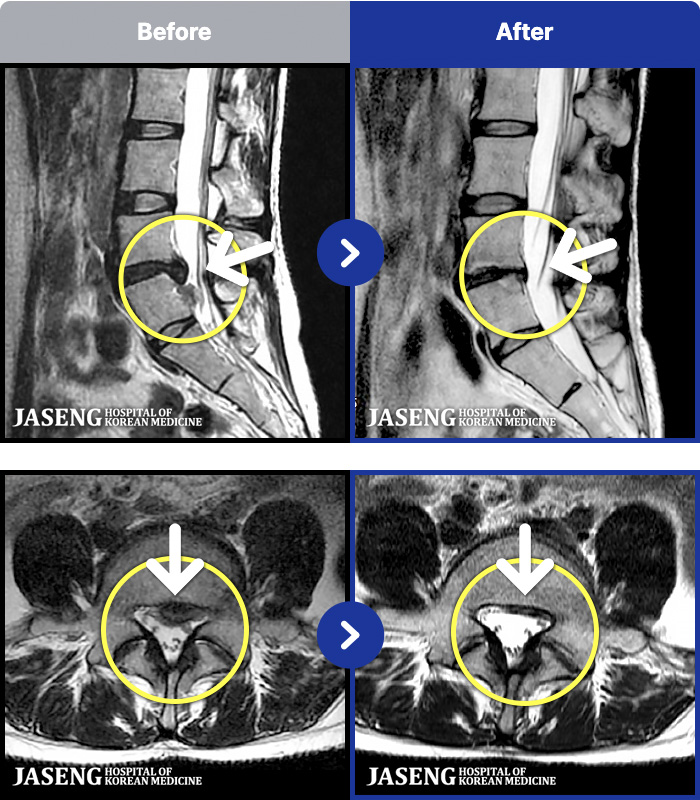

188 MRI ũ ʸ Ȯϼ.

ȯںп Ǹ ǿ ԿǾ, ο ġ ۿ Ƿ ġḦ Ͻñ ٶϴ.